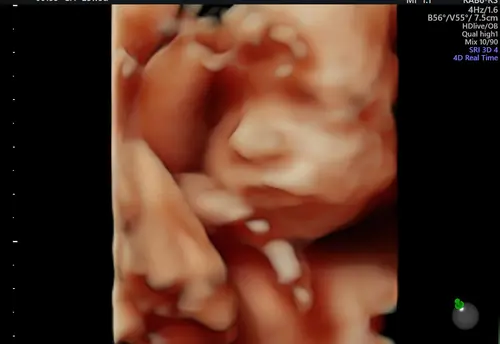

Ons menneke met 24 weken 💙

Wat een prachtig snoetje 😍